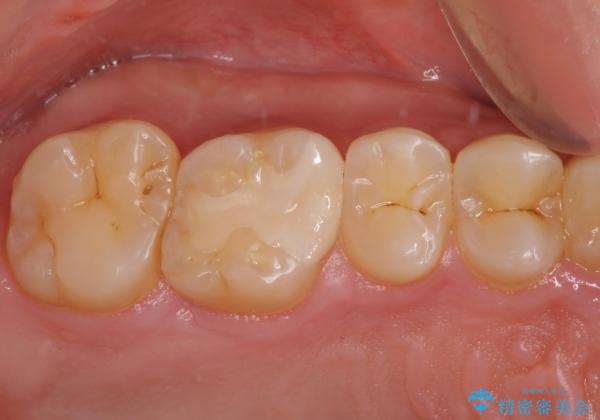

- 保険診療で治療した銀歯のやり替え希望の患者様です。

銀歯とその下の虫歯を除去し、形を整え、精度の良いシリコーンによる型どりを行いました。